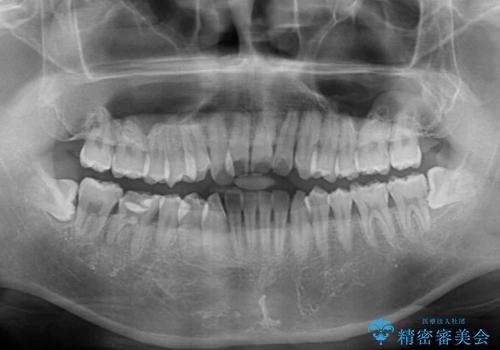

- 前歯のクロスバイトを気にして来院された患者様です。

デコボコやクロスバイトが散見されたため、IPR(歯と歯の間を削る)によってスペースを獲得できるように設計し、インビザラインにより治療を行うこととしました。

上顎側切歯(上の真ん中から2番目の歯)が舌側転位している場合、インビザラインでは仕上げきれない可能性があり、更には無理して動かそうとすると歯髄壊死を起こすリスクが高いと言われています。

安全に治療を行う対策として、インビザラインで歯列を移動する前に、上顎前歯をワイヤー矯正で整え、その後上下歯列をインビザラインにて矯正治療を行うプランを提案しています。